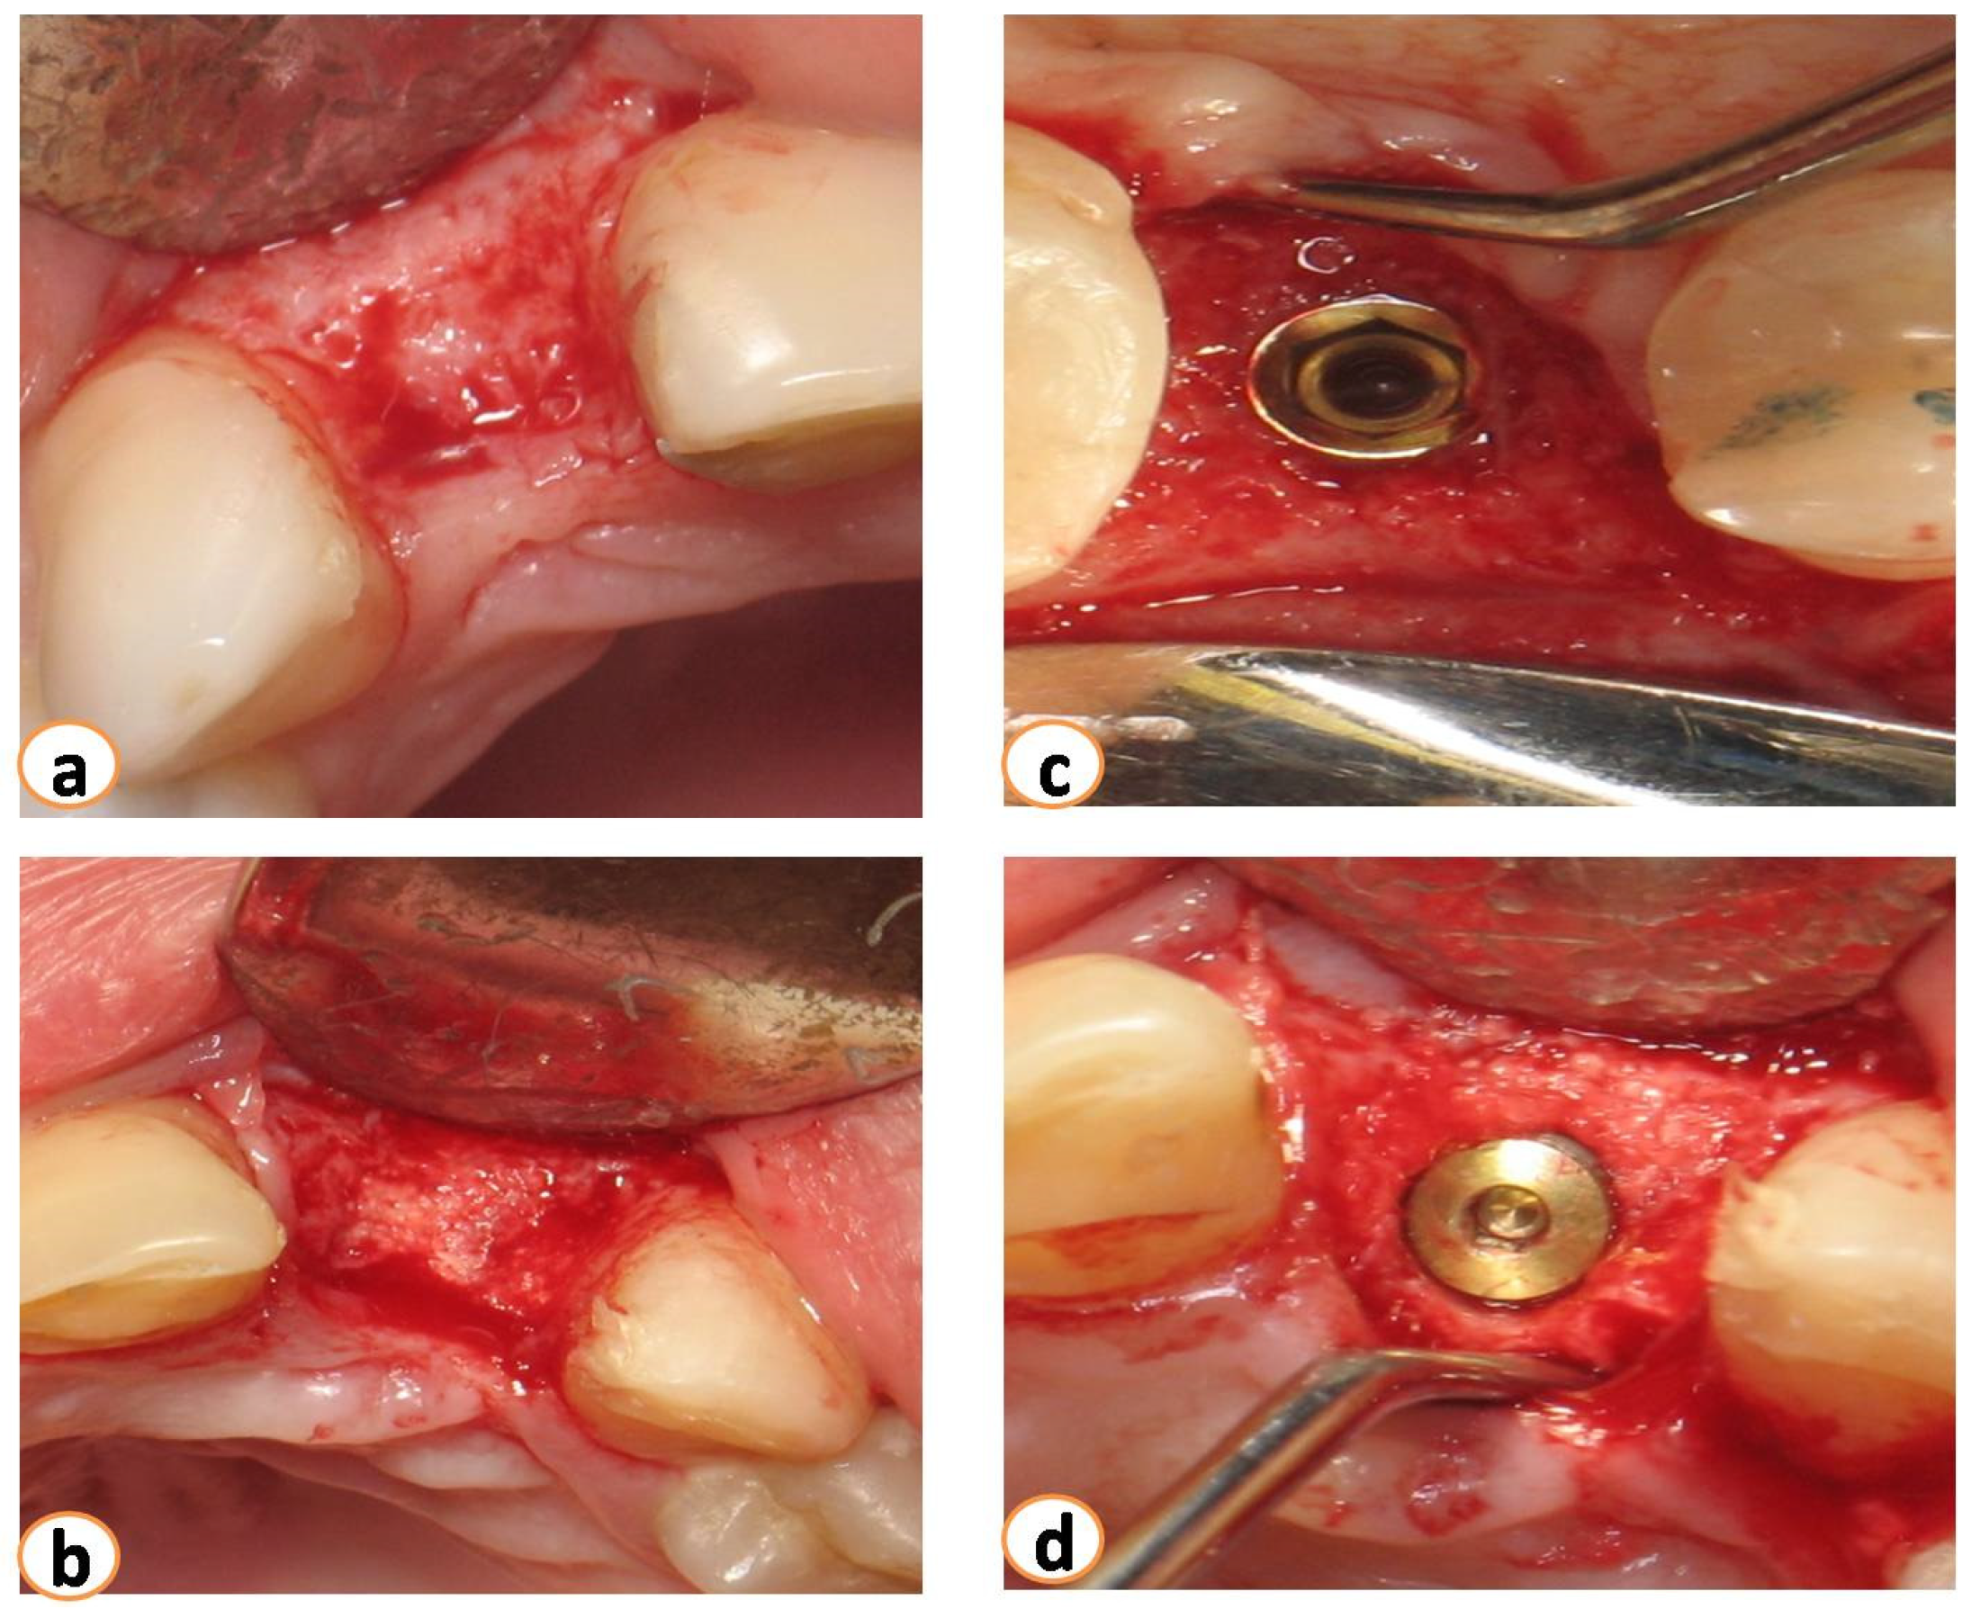

2.2. Surgical Procedures—Implant Rehabilitation